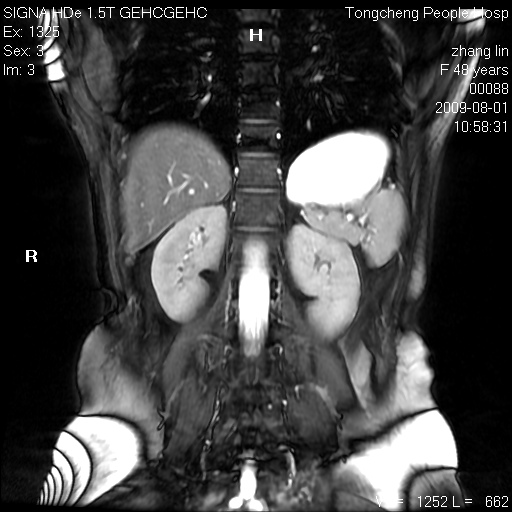

女,48岁。健康体检,彩超发现右肾占位性病变。平素健康。

临床诊断:右肾占位性病变,性质待定(囊肿?肿瘤?)。

上中腹部mr平扫+增强扫描,图像如下:

右肾上极见一类圆形病灶,t1wi呈等信号t2wi呈等高混杂信号,三期增强无强化,边界清---考虑囊肿出血。